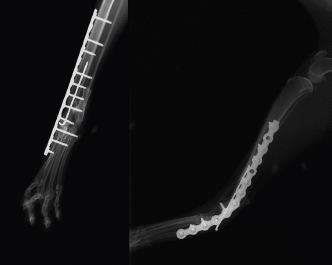

An 18-month-old female stray European cat was referred to the Veterinary Teaching Hospital of the University of Camerino, Italy. Anamnestic data reported a distal tibial epiphyseal sliding fracture (SH1) of the right hind limb inadequately treated 8 months prior with an intramedullary pin by colleagues and consequent chronic tarsocrural instability. Gait evaluation showed a non-weight bearing lameness (grade 4/5) of the right hind limb. An orthopedic examination revealed severe pain during the manipulation of the right tarsus, with bone crackling during stressed manipulation elicited by tibiotarsal joint laxity. Mediolateral and craniocaudal projections of the right tarsus showed failure of the fracture implant (intramedullary pin) caused by an inadequate choice of the apparatus and an incorrect osteosynthesis technique, with a caudomedial displacement of the right distal tibial epiphysis and a moderate process of bone remodeling and resorption (Fig. 1). The patient underwent pantarsal arthrodesis for the recovery of limb functionality. The anesthetic protocol included premedication with 3 μg/kg of dexmedetomidine (Dexdomitor 0.5 mg/ml; Orion Corporation, Finland), 0.3 mg/kg of methadone (Semfortan 10 mg/ml; Dechra, Italy), and 3 mg/kg of ketamine (Ketavet 100; Intervet Productions s.r.l., Italy) administered intramuscularly (IM). General anesthesia was induced with 4 mg/kg of propofol (Fresenius Kabi, Isola della Scala, Italy) administered intravenously (IV) and maintained with oxygen and isoflurane. When a good anesthesia plan was achieved, the femoral–sciatic nerve block was carried out with 0.2 ml/kg of lidocaine (Xylocaine 2%; Zidus Cadila, India). The affected limb and the contralateral foreleg were clipped, and a 4% chlorhexidine gluconate detergent was used for the preliminary preparation of the surgical sites, with a minimum contact time of 5 minutes. The patient was positioned in right lateral recumbency, with the affected limb toward the operating table and the contralateral limb fixed in the abduction position. Cefazolin (Cefazoline Teva; Teva s.r.l., Italy) was administered IV (22 mg/kg) approximately 30 minutes before the skin incision. Under complete aseptic precautions, the craniomedial approach was carried out to expose the tarsal joint. A skin incision, the same length as the plate, was made on the caudomedial aspect of the distal tibia and the craniomedial aspect of the tarsus and proximal metatarsus. The intramedullary pin was removed and sent to the laboratory for bacteriological examination. The tarsocrural, intertarsal, and tarsometatarsal joints were exposed, and the articular cartilage was removed with a high-speed burr. The autologous bone graft was collected from the cancellous bone of the contralateral humerus and was subsequently inserted into the joint spaces. After joint reduction, pantarsal arthrodesis was performed. A 1.2-mm Kirschner wire was driven through the calcaneus into the tibia, and a Compact UniLock 2.0 mandible locking plate (DePuy Synthes, Oberdorf, Switzerland) of 1.5-mm thickness was contoured to achieve the functional angle of tarsus extension and was positioned on the medial surface of the tarsus (Fig. 2). The plate was fixed with ten 2.0 mm locking screws and a cortical screw. The soft tissues were sutured by planes using a USP 3/0 absorbable monofilament thread. No tension at the suture lines was observed. The surgery lasted for 63 minutes. At the end of the surgery, an X-ray examination (Fig. 3) showed a good apposition of the fracture, with a slight internal rotation of the calcaneus; the apparatus seemed adequate, with a total plate screw density (PSD) of 0.85. The joint was fixed at 137° in extension. After radiographic examination, a soft padded bandage was applied for 14 days, which was renewed weekly. As needed, 0.3 mg/kg of methadone (Semfortan 10 mg/ml; Dechra, Italy) was administered IM for 24 hours postoperatively. Anti-inflammatory therapy (meloxicam 0.05 mg/kg; Metacam 40 mg/ml; Boehringer Ingelheim Vetmedica, Germany) and ranitidine (2 mg/kg; Zantadine 30 mg/ml; Ceva s.p.a., Italy) IV were administered on an inpatient basis. The first orthopedic evaluation, the first day after surgery, showed an improvement in gait (grade 2/5 of lameness on walk). The cat was discharged from the hospital after 3 days with a prescription of anti-inflammatory and analgesic therapy. The head of the cat shelter was instructed to subject the cat to cage rest for 30 days. At the first follow-up, 7 days after surgery, the soft padded bandage was renewed, and the cat showed a steady improvement in gait. Fourteen days after surgery, the soft bandage was removed; the orthopedic examination showed mild improvement in gait, although second-degree lameness and an extended tarsal and flexed stifle gait persisted because of the arthrodesis procedure. No swelling or dehiscence at the surgical site or skin tension under the plate was observed; the suture was removed, and the cat was discharged with light exercise on a larger cage recommendation for the remaining 15 days. One month after surgery, at the orthopedic evaluation, the head of the cat shelter reported a slight worsening of lameness after a sharp jump had occurred 7 days prior. The patient showed good limb function, with a slight worsening of gait during the trot, and the radiographic evaluation showed good bone activity, with 50%–66% of the joint fusion and fracture healed, although a metatarsal stress fracture was revealed (Fig. 4). Four months after surgery, radiographs revealed stable implants and an almost complete fusion of the joints (Fig. 5). The surgical wound site, 30 and 120 days after surgery, healed very well, with an efficient aesthetic result of the limb, even with a slight loss of skin elasticity, which occurs naturally after surgery. The patient never showed discomfort at the implant site, even though the plate was very superficial and palpable under the thin skin (Fig. 6). Moderate free activity with gradual introduction to freedom in the feline colony was prescribed.

Fig. 5. Radiographic follow-up examination 16 weeks after pantarsal arthrodesis revealing an almost complete fusion of the arthrodesis.